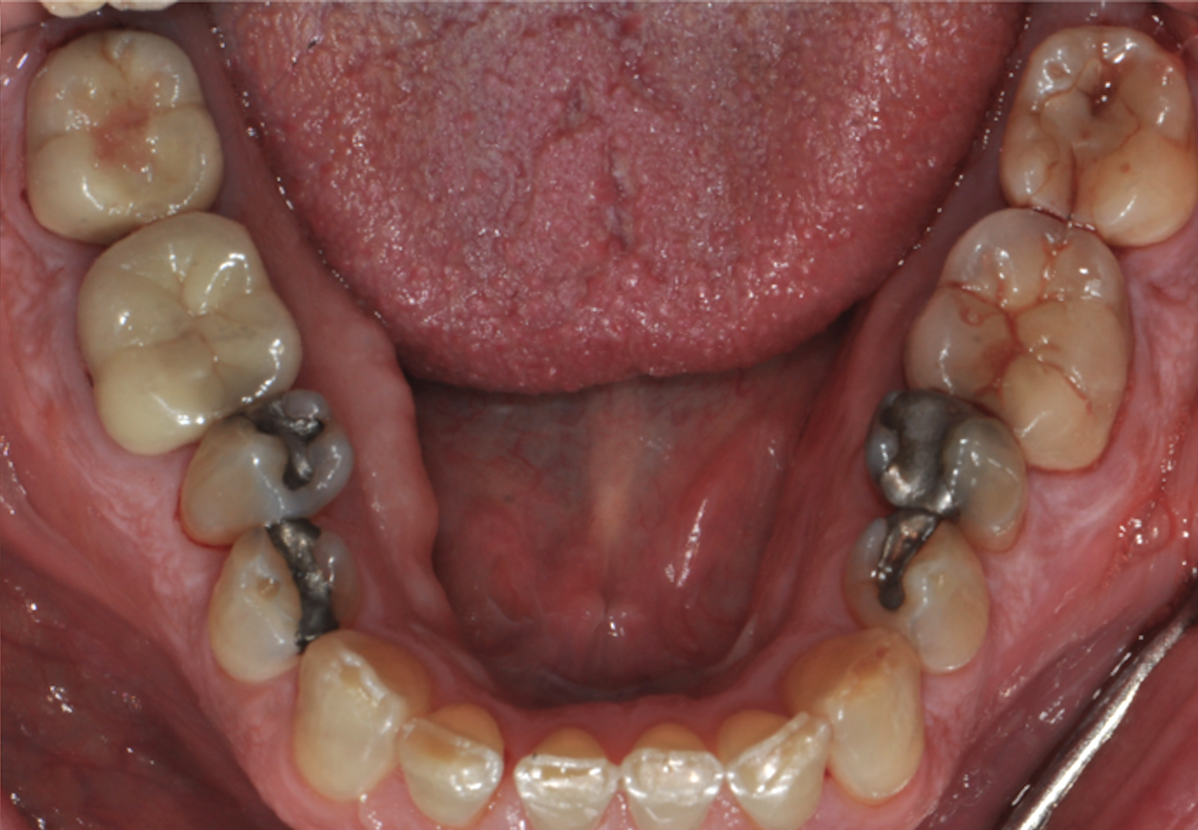

Fig 5. Pretreatment occlusal views: maxilla (Fig 5) and mandible (Fig 6).

Figure 5

Fig 6. Pretreatment occlusal views: maxilla (Fig 5) and mandible (Fig 6).

Figure 6

Periodontal examination revealed generalized BOP and PDs up to 9 mm in the maxillary and mandibular molars with multiple furcations in each molar (Figure 2 through Figure 7). He presented with class I mobility in many posterior teeth and class II mobility in teeth Nos. 3 and 9 (maxillary right first molar and maxillary left central incisor, respectively). The periodontist decided to score tooth No. 3 for the PRS, as this was the most periodontally involved molar that was planned to be treated and maintained (Figure 2 and Figure 8). This tooth (maxillary right first molar = score 1) presented with probing depths of 7 mm (score 1); three total furcation invasions (score 3) (mesial [degree II furcation], buccal [degree I furcation], and distal [degree II furcation]); and a class II mobility (score 2). The total PRS for tooth No. 3 was 8, representing a "guarded" prognosis. Based on this score, the likelihood of not losing any teeth to periodontal disease for 15 years was 81%, and for 30 years the likelihood was just 56% (Figure 9).7